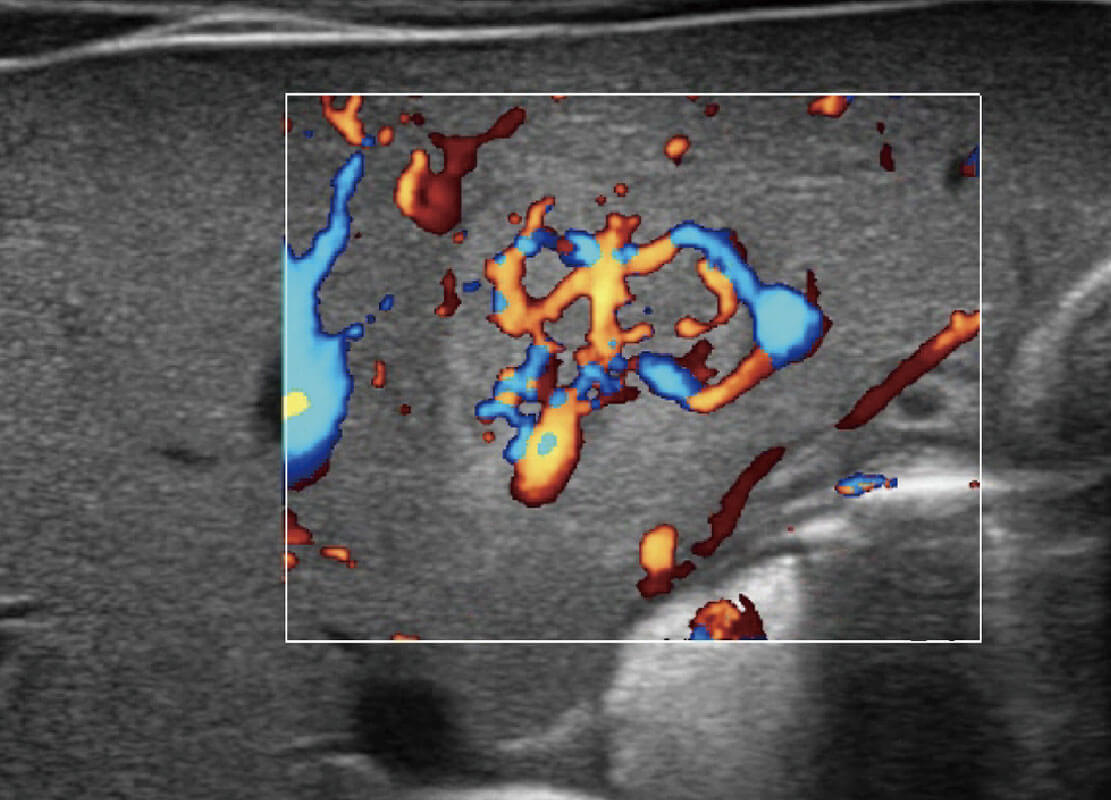

乳腺癌显微血流

P60搭载宽频带线阵探头、宽景成像、弹性成像技术,为您提供乳腺应用方案。P60支持高频相控阵探头、线阵探头、腹部高频探头、腹部微凸探头等,丰富的探头群搭载敏感的彩色血流成像,适用于新生儿多种脏器检测要求,满足新生儿筛查需求。